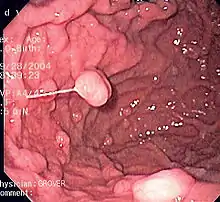

- يعد التنظير الهضمي طريقة أخرى لفحص المعدة.

صورة تنظيرية لداء البوليبات الغدي.